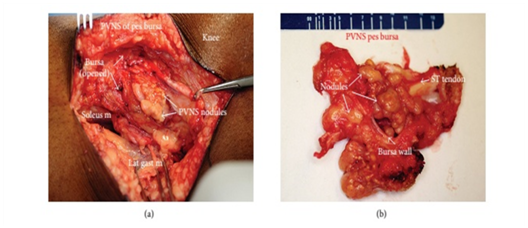

Grossly, pigmented villonodular synovitis appears as a proliferative synovial process with brownish villo-nodular fronds in the affected joints (Figure 3).2 Multiple yellow to brown nodules could be detected in localized types and in the pes anserine bursa (Figure 4). Histopathologically, the tumor is generally represented by many mononuclear histiocytic cells and irregularly interspersed multinucleated giant cells. Hemosiderin pigments could also be detected. Some foamy histiocytic cells may individually interspersed or form clusters (Figure 5).8 Osseous, cartilaginous, and soft tissue involvement was also seen .Fine needle aspiration cytology reveal a few clustered and scattered plump spindle cells containing hemosiderin-pigments and several scattered multinucleated giant cells (Figure 6).

Figure 4 Intraoperative photograph of the lesion (a) and Gross specimen showing multiple yellow to brown nodules inside the pes anserine bursa (ST: semitendinous tendon) (b).